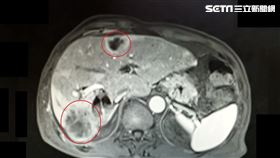

快來看!你是不是肝內管癌高風險族群

65歲的許先生本身有糖尿病、BC型肝炎帶原與肝內管結...